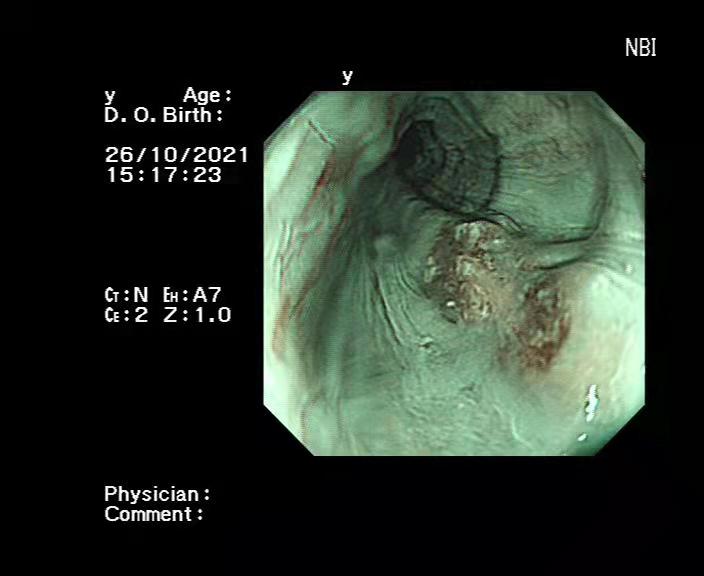

患者男性,71岁,常规胃镜早癌筛查中发现食管病灶,经活检病理证实为食管高级别上皮内瘤变。进一步行放大内镜及超声胃镜检查,判断病灶局限于食管黏膜下层,可行内镜下黏膜剥离切除术。

2021年11月2日上午,在胸外科陈于平主任、李桦副主任医师和内镜室负责人郭毅的带领下,胸腔镜和消化内镜双镜联合。术中定位病灶,黏膜下注射隆起,内镜下切除病灶。术程顺利,病灶被完整切除。患者恢复快,5天后出院。